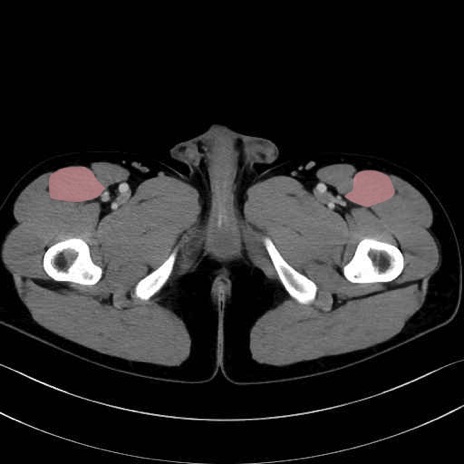

5. 大腿前面(大腿四頭筋群・伸筋群)

縫工筋 (Sartorius)

大腿直筋 (Rectus femoris)

外側広筋 (Vastus lateralis)

中間広筋 (Vastus intermedius)